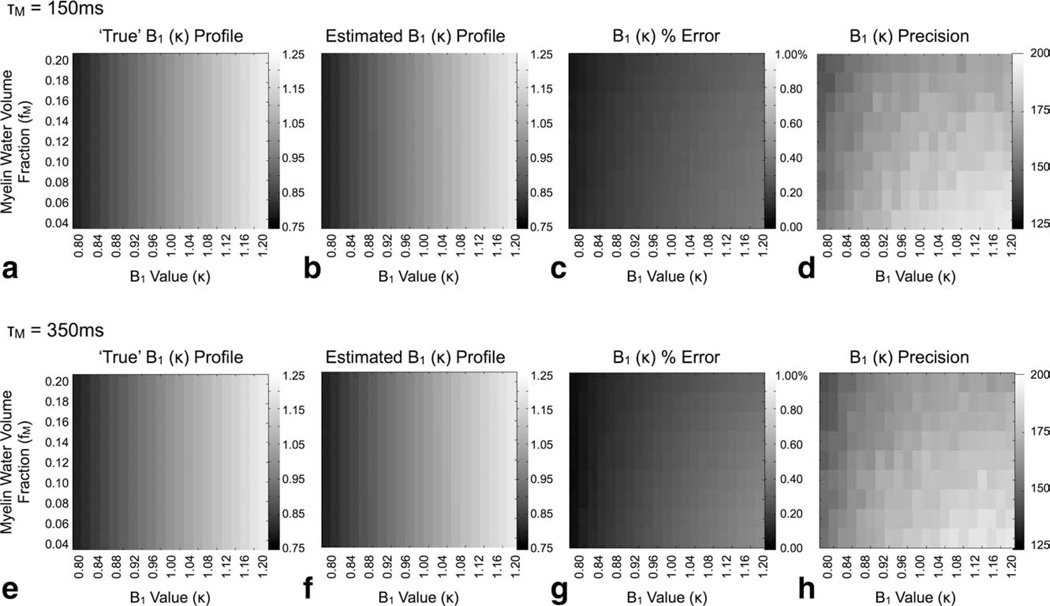

Results of our investigation of the accuracy of DESPOT1-HIFI κ estimates derived from two-relaxation component data assuming a single-component T1 model are shown in Fig. 5. For both residence times investigated (150 and 350 msec) the method provides accurate κ estimates, with less than 1% error, over the full range of κ and fM investigated despite assuming a simplified T1 relaxation model.

FIG. 5.

Simulation results showing the accuracy (percent error) and precision of calculated flip angle calibration factors (κ) using the DESPOT1-HIFI approach with two-relaxation component SPGR and IR-SPGR data. For both exchange times investigated, the method shows high B1 accuracy despite assuming single-component relaxation. The grayscale values in (a), (b), (e), and (f) correspond to the B1 value at each point in the 2D grid.